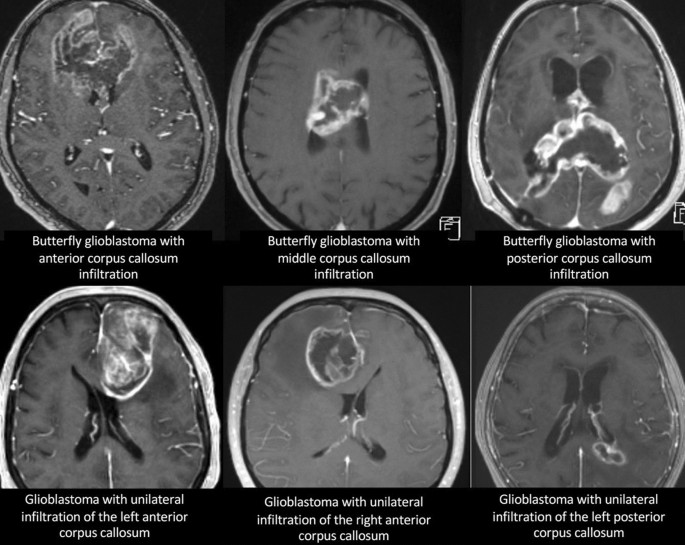

Table 2 summarizes the data on surgical and adjuvant treatments in the patient groups. Most patients received adjuvant treatment according to Stupp protocol, which was comparable between both groups (67% vs. 63%). The proportion of patients, who completed the treatment according to the Stupp protocol did not significantly differ between both groups (41% vs. 37%). In 10% of all patients a treatment according to the Stupp protocol was recommended but no information was available whether the treatment was indeed carried out or not due to lost to follow-up. The surgical approach differed significantly between glioblastoma with unilateral corpus callosum infiltration and glioblastoma with bilateral corpus callosum infiltration with larger proportion of biopsy in glioblastoma with bilateral corpus callosum infiltration compared to glioblastoma with unilateral corpus callosum infiltration, and gross total resection only performed in glioblastoma with unilateral corpus callosum infiltration. Gross total resection was performed in patients either with infiltration of the anterior corpus callosum (54%, 15/28) or the posterior corpus callosum (46%, 13/28). An infiltration of the middle corpus callosum was considered unsuitable for resection due to eloquent location. Examples of different tumor locations and surgical decisions are given in Fig. 1. At 6-month follow-up a tumor recurrence was found in 67.8% of the patients, who initially underwent tumor gross total resection, of whom 47.3% had a local recurrence at the edge of the former resection cavity, 42.2% developed a distant recurrence, and 10.5% had a recurrence within the contralateral corpus callosum.